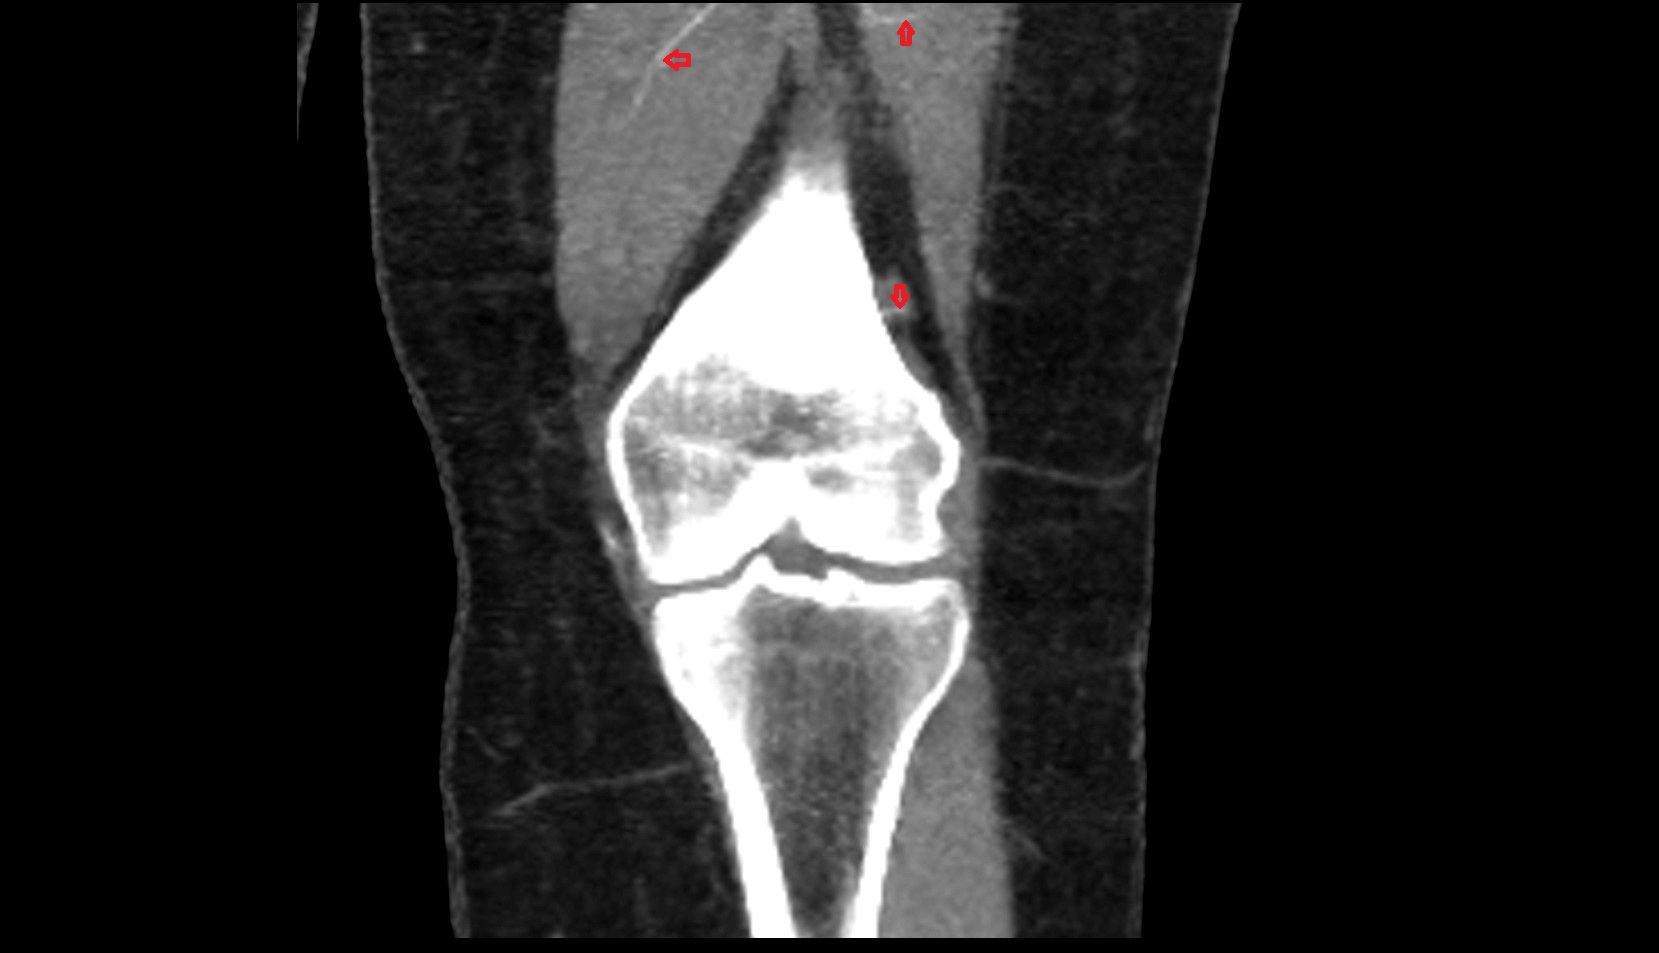

- Knee Joint